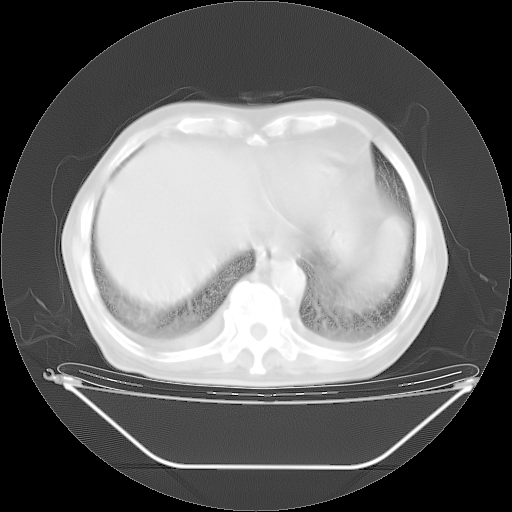

胸腹部CT,诊断意见:左上肺叶钙化灶、左侧胸膜局限性增厚并钙化、胆囊炎。描述部分肺组织呈磨玻璃样改变。